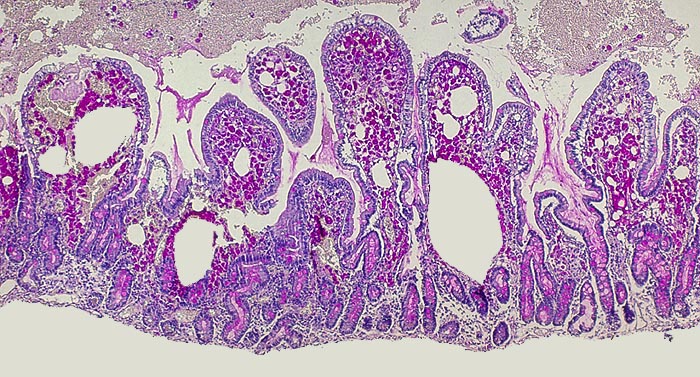

PathoPic ID 1838 - Morbus Whipple

Morbus Whipple

Entzündung infektiös

Duodenum

Darm, Anus

Massive Infiltration der Mukosa durch PAS positive Makrophagen. Die Hohlräume entsprechen Lymphangiektasien.

Histologie